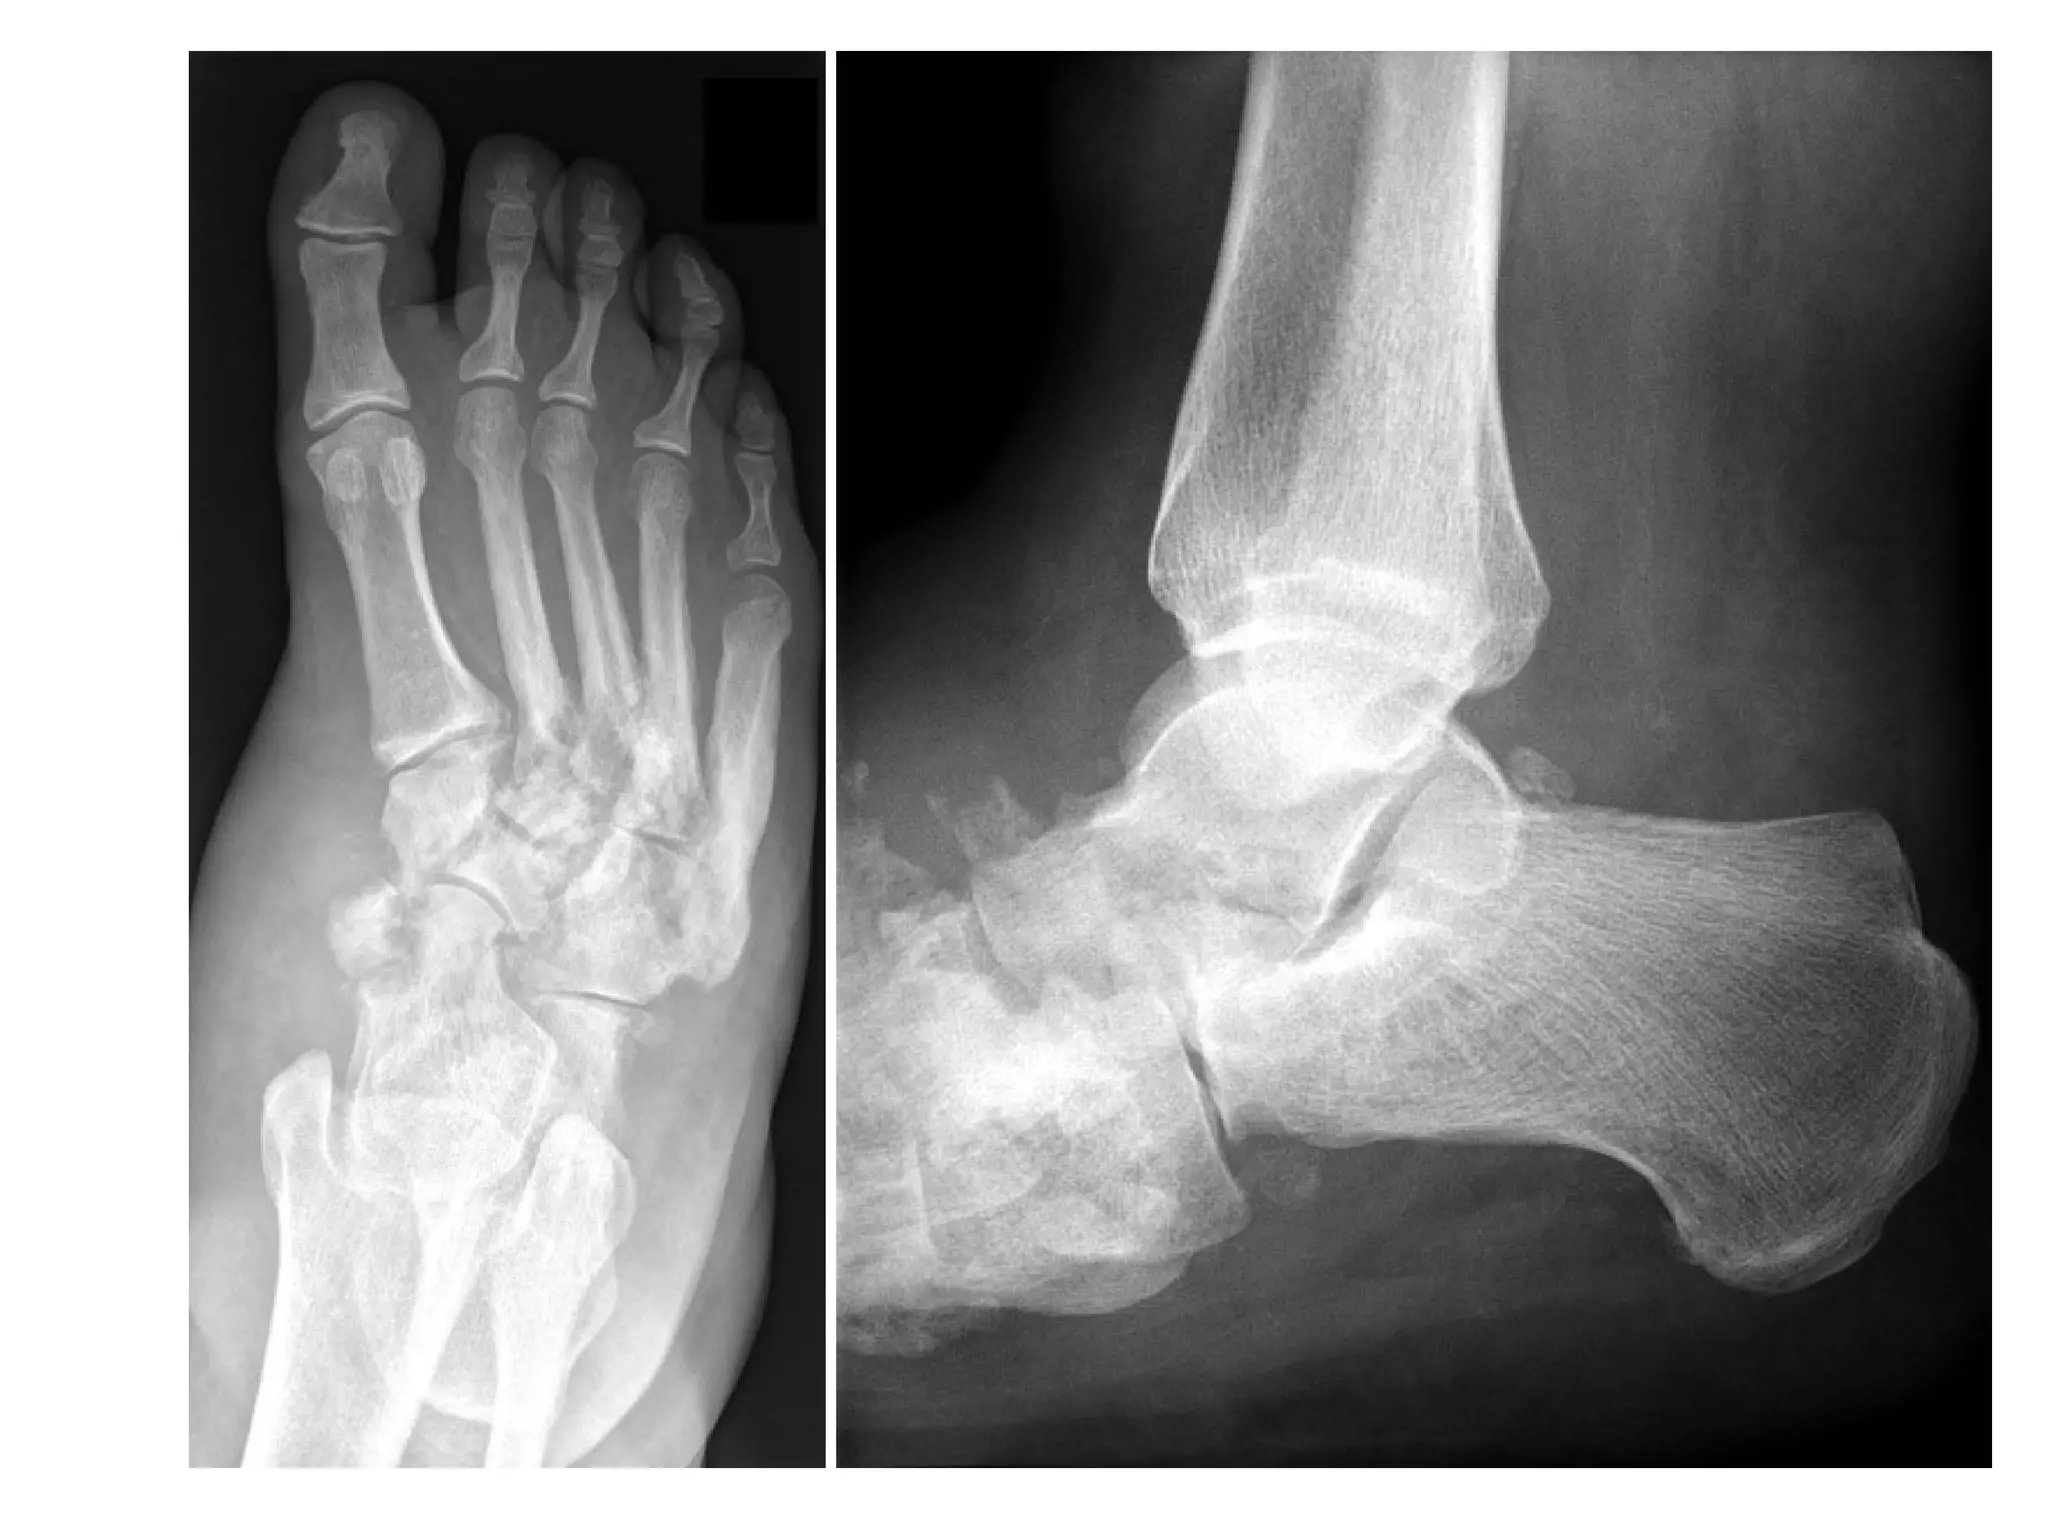

Lateral view of the hindfoot shows ill-defined plantar calcaneal enthesophytes (arrowhead) , periosteal

new bone formation along the posterior aspect of the distal tibia (arrow) , retrocalcaneal bursitis

and thickening of the Achilles tendon (star) and erosions at the subjacent calcaneus

Periosteal reaction at the plantar fascia insertion (black arrow) and

early erosion at the Achilles tendon insertion (white arrow) on the

calcaneus